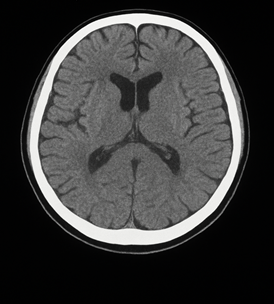

Timeline of Care

Intravenous immunoglobulin (IVIG): 2g/kg administered over five consecutive days, providing therapeutic antibodies to modulate the autoimmune response [3,11].

Plasma exchange: four sessions conducted over one week (200-250 ML plasma /Kg body weight per session) to remove pathogenic circulating antibodies [4,12].

Inpatient rehabilitation progress (weeks 3-12)

Upper body strength improvement: 2/5 to 4/5

Lower limb strength improvement: 1/5 to 3/5

Progressive sensory recovery

Achieved independence in most daily activities

Transitioned from total dependence to minimal assistance with transfers

Achieved short-distance ambulation with walker assistance

Improved swallowing ability, allowing for soft diet intake

Significant speech clarity improvement

Three-month follow-up

Continued strength and endurance improvement

Occasional neuropathic pain in the feet

Mild residual lower limb weakness

Independent ambulation for longer distances without assistive devices

Minimal foot drop requiring ankle-foot orthosis for extended walking

Enrolled in a long-term outpatient therapy program

Overall prognosis assessed as fair to good, with continued gradual recovery expected

Returned to teaching